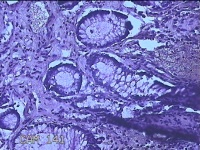

性别

男

年龄

40岁

临床诊断

混合痔

一般病史

反复肛门肿物突出15年。

标本名称

肛门肿物

大体所见

灰白暗红色肿物0.7x0.5x0.2cm一个,表面糜烂。

脱水、透明,浸蜡、脱蜡效果不佳,制片质量差。